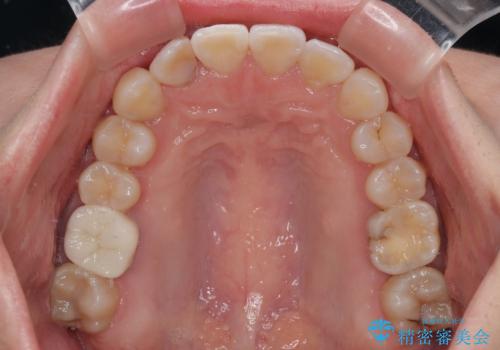

適合や携帯の悪いプラスチックのクラウンが装着されていたため、矯正治療後にオールセラミッククラウンによる補綴治療を行うこととしました。

当初予定通り1年半ほどの治療期間で、非常に綺麗な歯列に仕上げることができました。